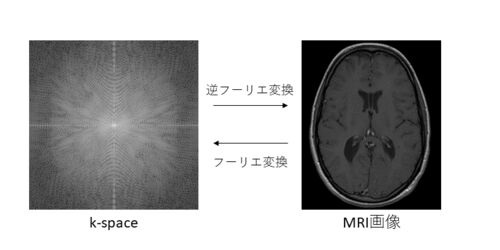

k-spaceはよくこんな感じで説明されてます. k-spaceはMRIで受信した信号を格納したものと私は理解してます.k-spaceを逆フーリエ変換するとMRI画像が取得できます. ところで,大手医療機器メーカーが販売しているMRI装置では,ユーザーは基本的にk-spaceを…